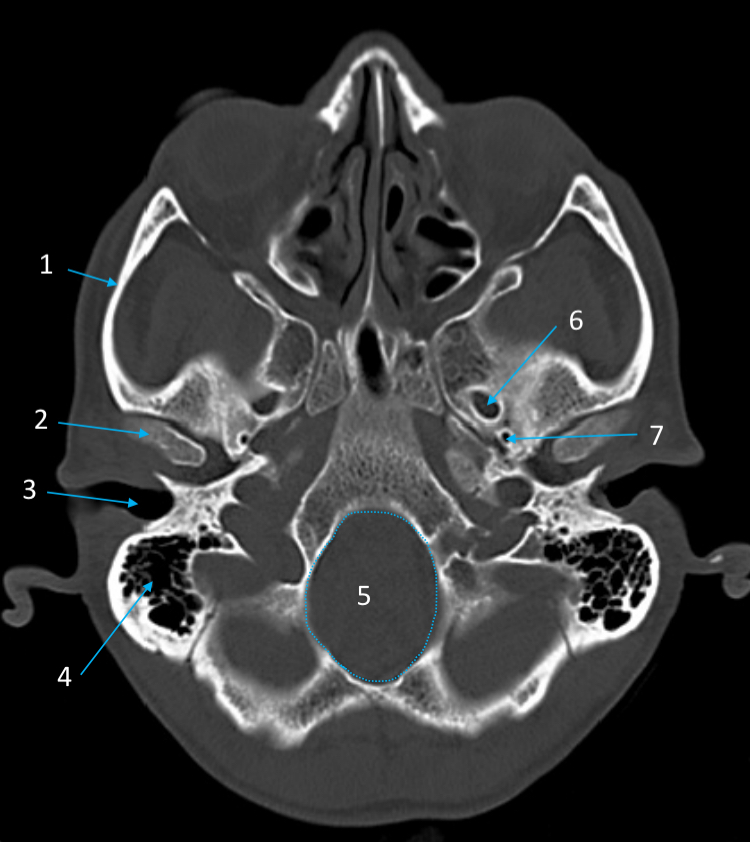

Mandible

ID bone

Maxilla

ID bone

Frontal sinus

ID structure

Pituitary fossa

ID structure

Occipital

ID bone

Lambdoid suture

ID structure

Frontal sinus

ID structure

Orbital margin

Orbit

Maxillary sinus

ID structure

Mandibular condyle

ID structure

Inferior nasal concha

ID structure

Hard palate

ID strucutre

Gonial angle

ID strucutre

Petrous ridge

ID structure

Groove of middle meningeal a.

ID structure

Roof of orbit

ID structure

Frontal sinus

ID structure

Pituitary fossa

ID structure

Petrous ridge

ID structure

Sphenoid sinus

ID structure

Hard palate

ID structure

Mastoid air cells

ID structure

Zygomatic arch

ID structure

Mandibular condyle

ID structure

External auditory meatus

ID structure

Mastoid air cells

ID structure

Foramen magnum

ID structure

Foramen ovale

ID structure

Foramen spinosum

ID structure